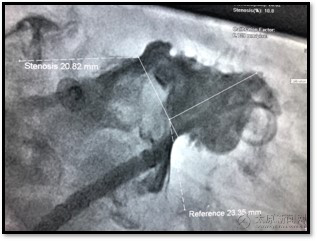

▲肝位造影充分顯示心耳形態,DSA影像與術前CT形態相符,為多分葉菜花狀。

▲DSA下測量,心耳開口約20mm,深度約23mm,選取24mm WATCHMAN左心耳封堵器。